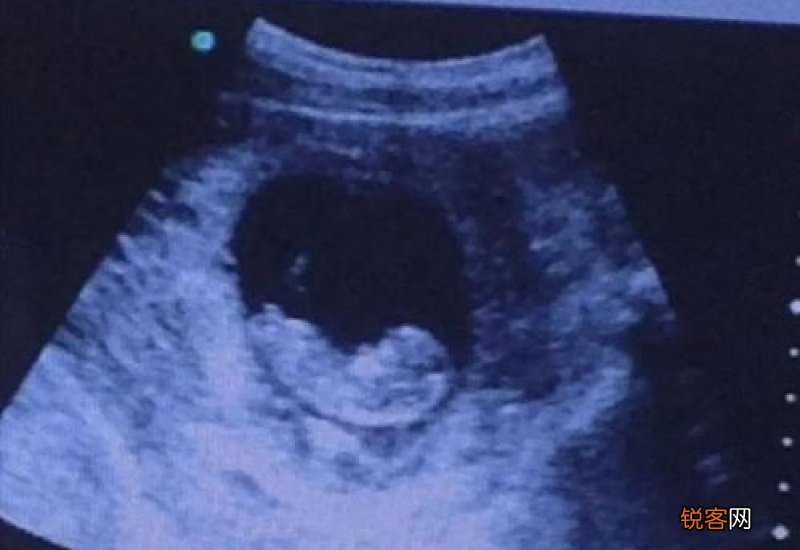

【怀孕了可以打九价吗】 如果是已经怀孕的人,最好不要接种九价疫苗 , 因为疫苗产生不是很稳定 , 所以可能会对孕妇或者胎儿有一定的影响 , 建议不要打最好,如果是在不知道自己怀孕的情况下打了的话 , 建议去医院进行产检,如果产检正常的话,一般没事 。